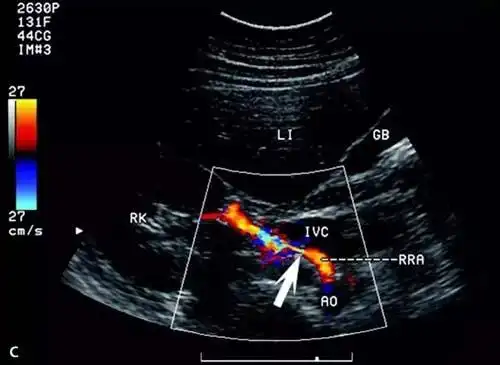

最简单的诊断办法是进行多普勒超声检查,彩超省时,无创,经济,可初步